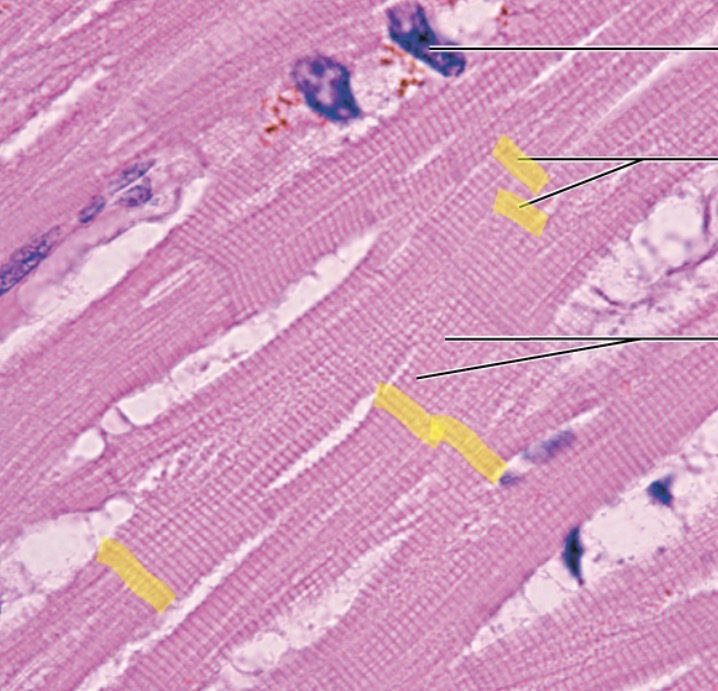

Heart

Intercalated Discs